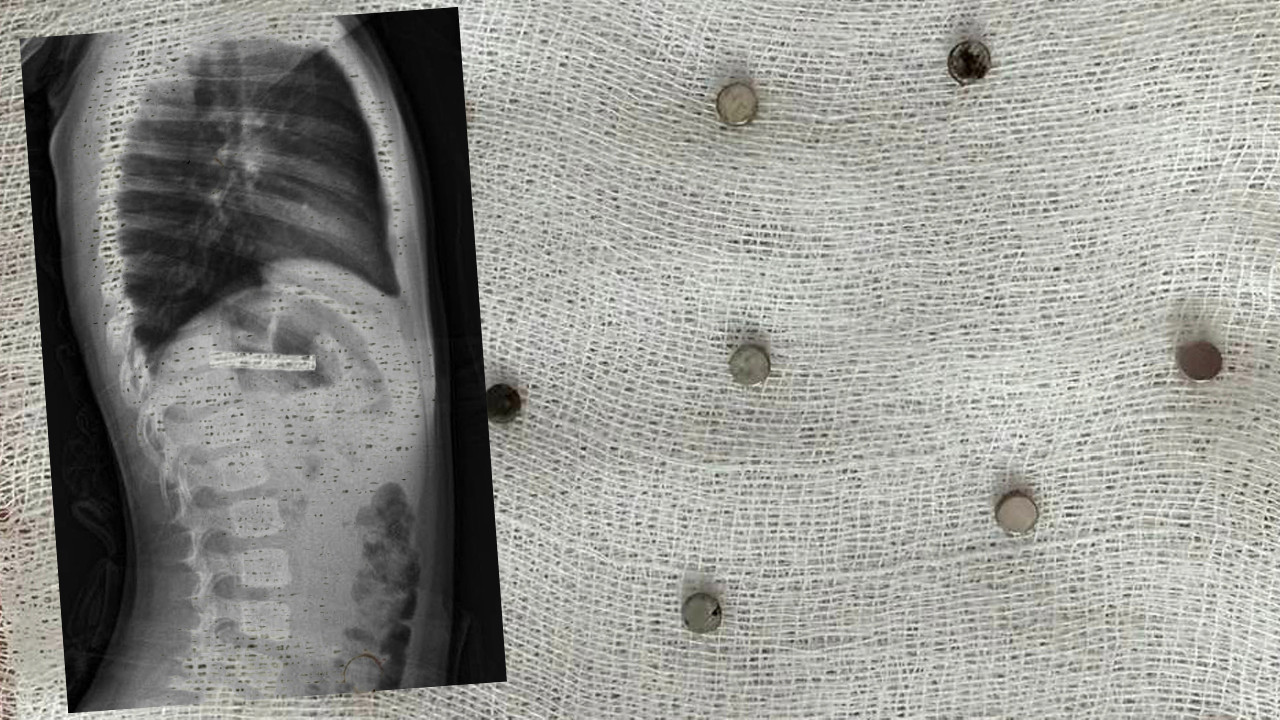

Erzurum'da ailesinin rahatsızlandığı için hastaneye götürdüğü 3 yaşındaki çocuk herkesi şoke etti. Küçük çocuğun boğazından tam 19 adet mıknatıs çıkarıldı.

Erzurum’da iddiaya göre, 3 yaşındaki çocuk evde bulunan 19 tane mıknatısı yuttu. Çocuğun rahatsızlanması sonucu durumu öğrenen aile hastaneye gitti. Daha sonra çocuk Elazığ’a sevk edildi.

Fırat Üniversitesi Çocuk Gastroenteroloji Hepatoloji ve Beslenme Bilim Dalı Başkanı Prof. Dr. Yaşar Doğan, çocuk hastanın yemek borusuna yapışmış 19 mıknatısı endoskopik yöntemle çıkardı.

Küçük çocuğun yuttuğu mıknatıslar

Mıknatıslar uzun süre yemek borusunda takılı kaldığı için yemek borusu ve mide girişinde zedelenmeler olurken, çocuğun sağlık durumunun iyi olduğu ve taburcu edildiği öğrenildi.